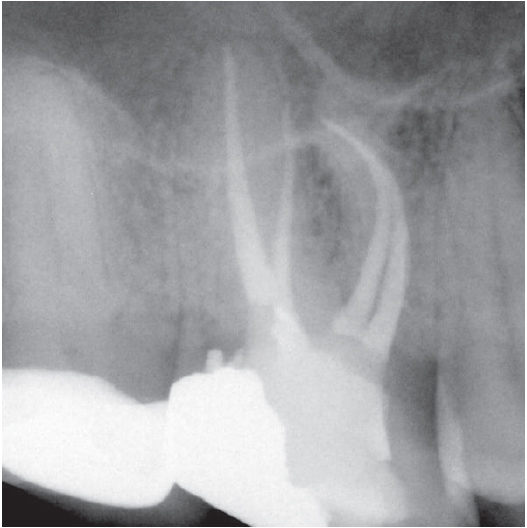

Before

Before Root Canal treatment